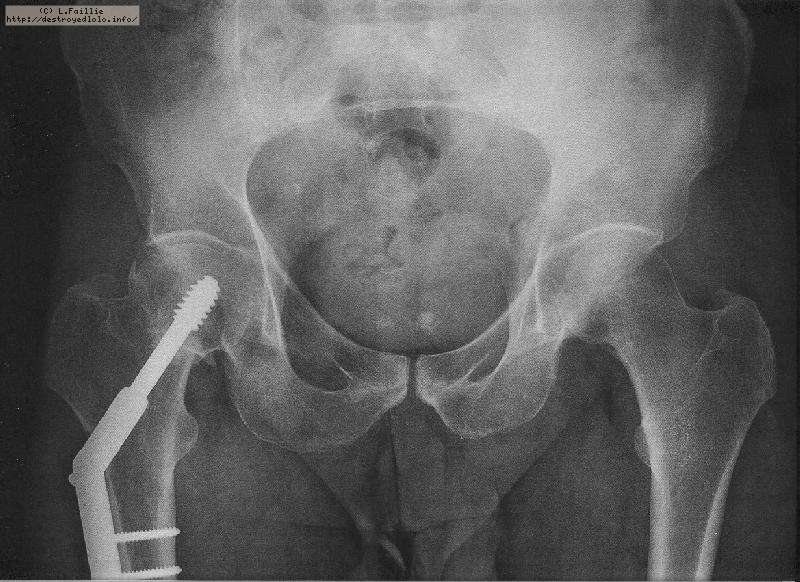

La saison est finie : fracture du col du fémur :(

Pompier, hôpital, 3 mois alités ...